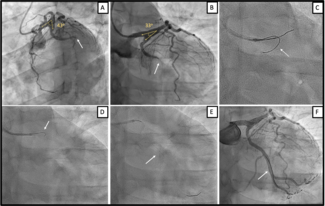

A 50-year-old man with family history of coronary artery disease underwent primary percutaneous coronary intervention due to an inferior ST-elevation myocardial infarction. Coronary angiography revealed an occluded left circumflex artery.